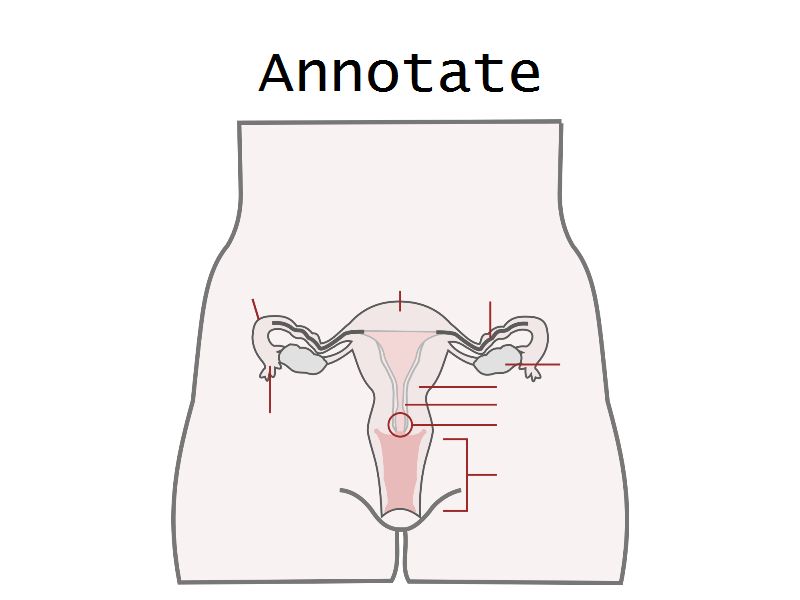

Uterus

Slide 88

Uterus

3 regions3 layers

Three regions

FundusBody

Cervix

Three layers

- Endometrium

- Formation placenta

- Myometrium

- Enlarge during pregnancy

- Expulsion fetus & placenta

- Adventitia

Vagina

Slide 90

Vagina